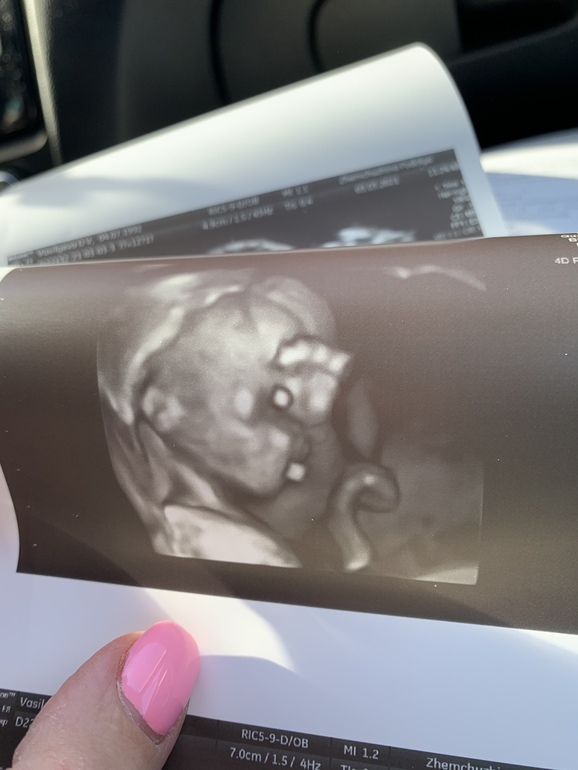

Недавно выкладывала фото узи,спрашивала у вас-мальчик или девочка?)

Так вот в 10 недель нам предположили парнишку,а сегодня,на первом скрининге сказали -ПОКА девочка😁

В общем до сих пор не очень понятно,но уж очень хочется дочку)

P.S.с малышом все хорошо,никак не хотел показывать носик-крутили,вертели меня,в итоге на долю секунды малыш повернулся)